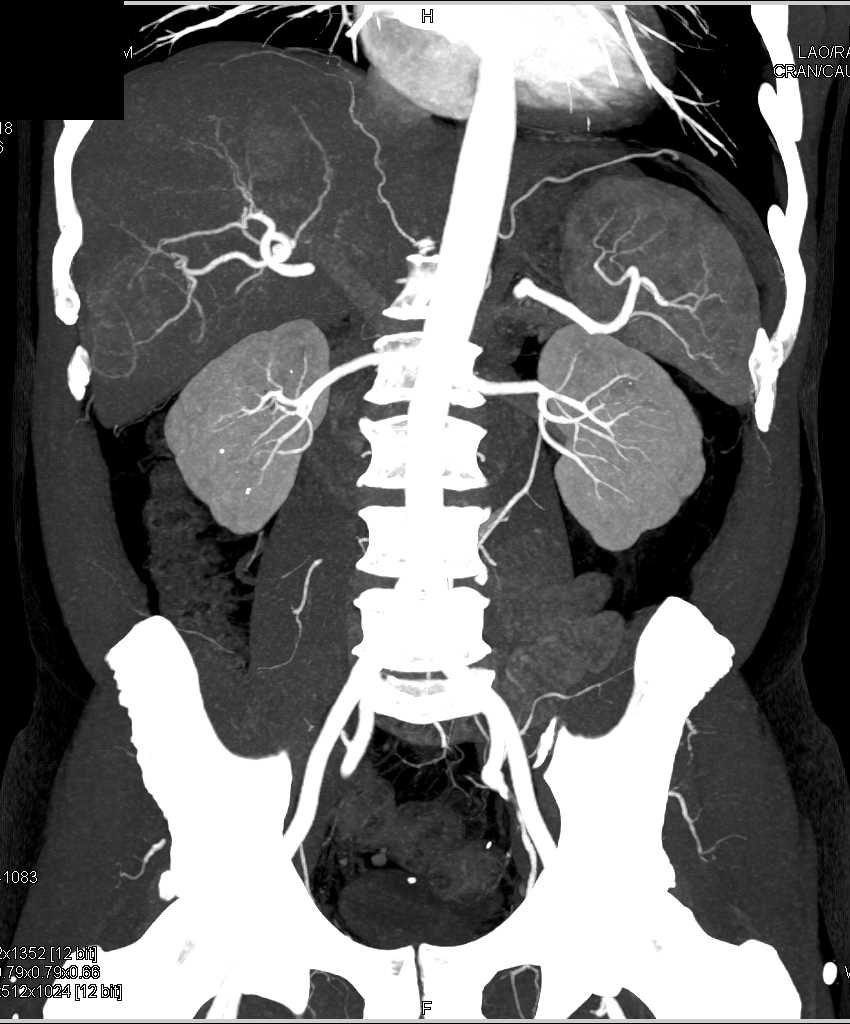

Carcinoid Tumor with Desmoplastic Reaction